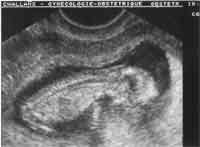

Vaginale